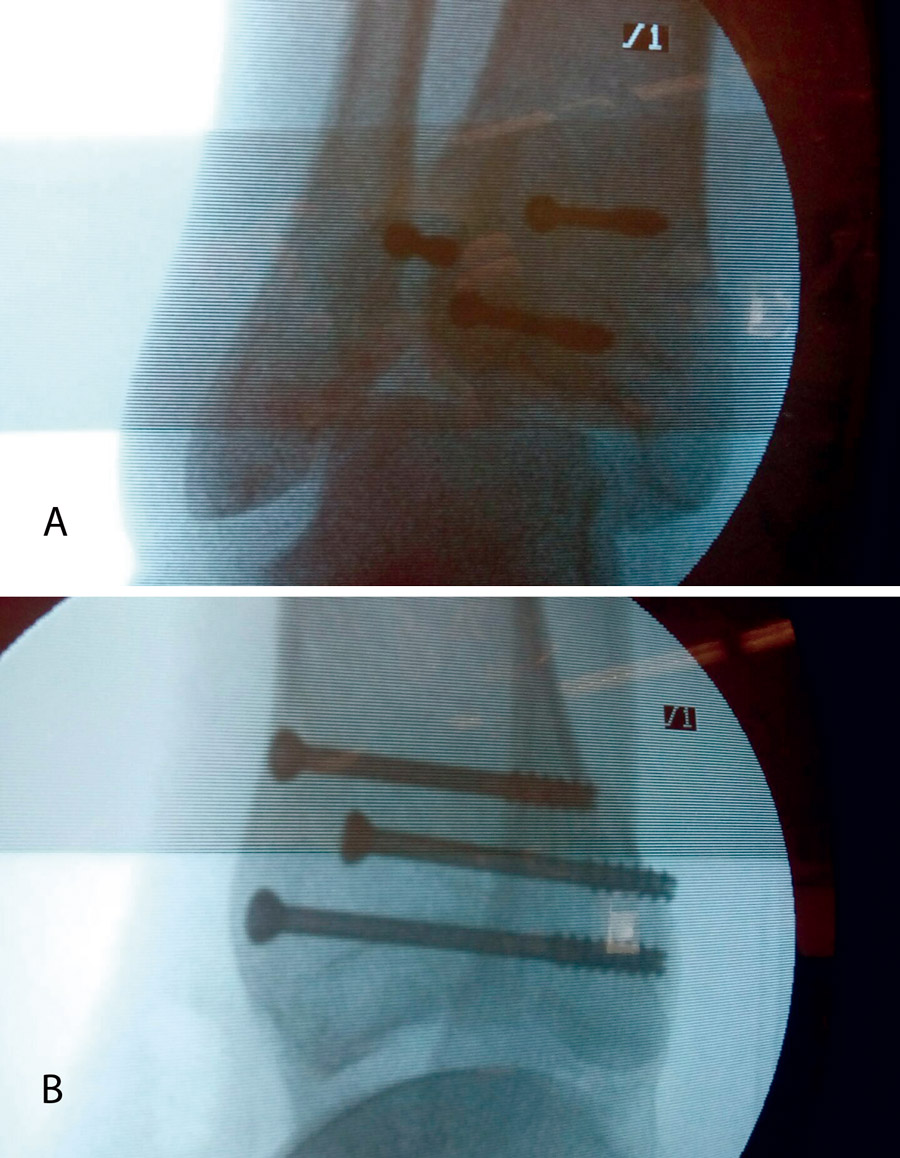

Realizamos los portales artroscópicos habituales en función de la situación de los extremos óseos de la fractura y practicamos un procedimiento idéntico al anterior: lavado, desbridamiento e identificación del foco de fractura (Figuras 12 a 16).

Figura 12. Caso 2: fractura espiroidea con afectación articular. Posicionamiento en férula de Braun. Tracción con vendas. Realización de portales.

Figura 13. Posteriormente, realizamos la limpieza del foco con cucharilla y la reducción del mismo mediante pinzas de cóndilo bajo control radioscópico/artroscópico, y fijación provisional con agujas de Kirschner.

Figura 14. A continuación, se realiza la medición y colocación secuencial de los tornillos.

Figura 15. Por último, se procede a la colocación definitiva de los tornillos.

Figura 16. Resultado final a los 4 meses.